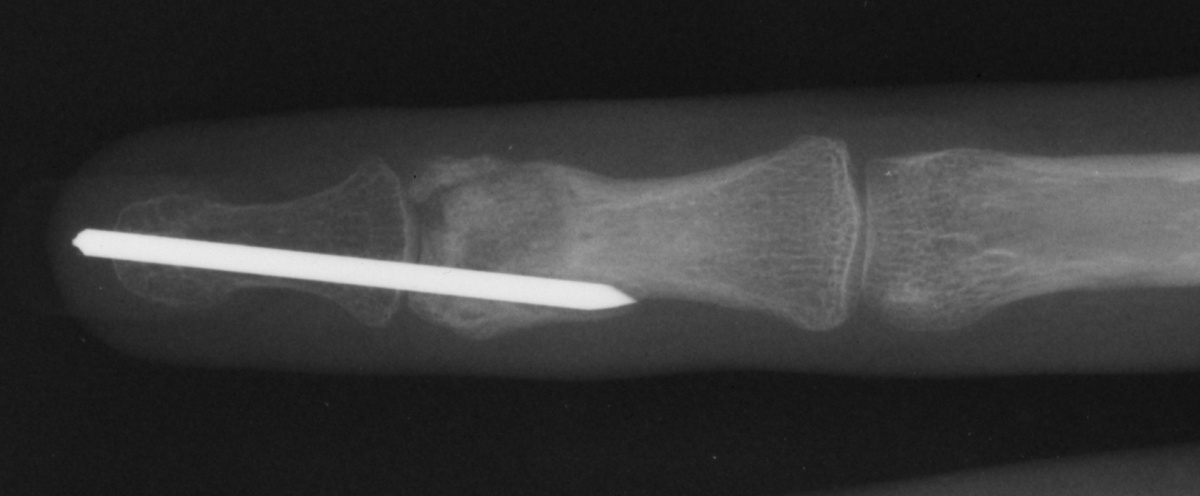

| Case 1. This 18 year old man

presented with a two year history of pain and swelling of the distal

aspect of his proximal phalanx. |

| Plain films showed

sclerosis within a radiolucent area and adjacent cortical/endosteal

sclerosis. |